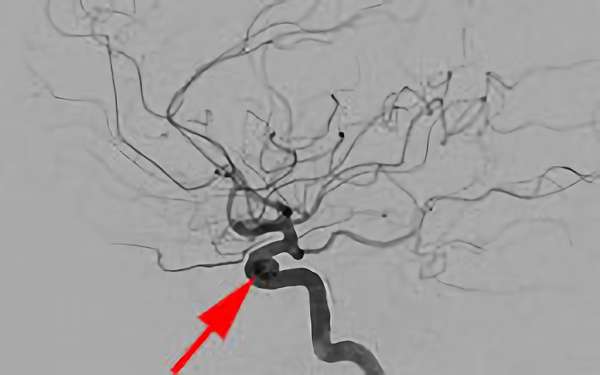

No.1631 手術後